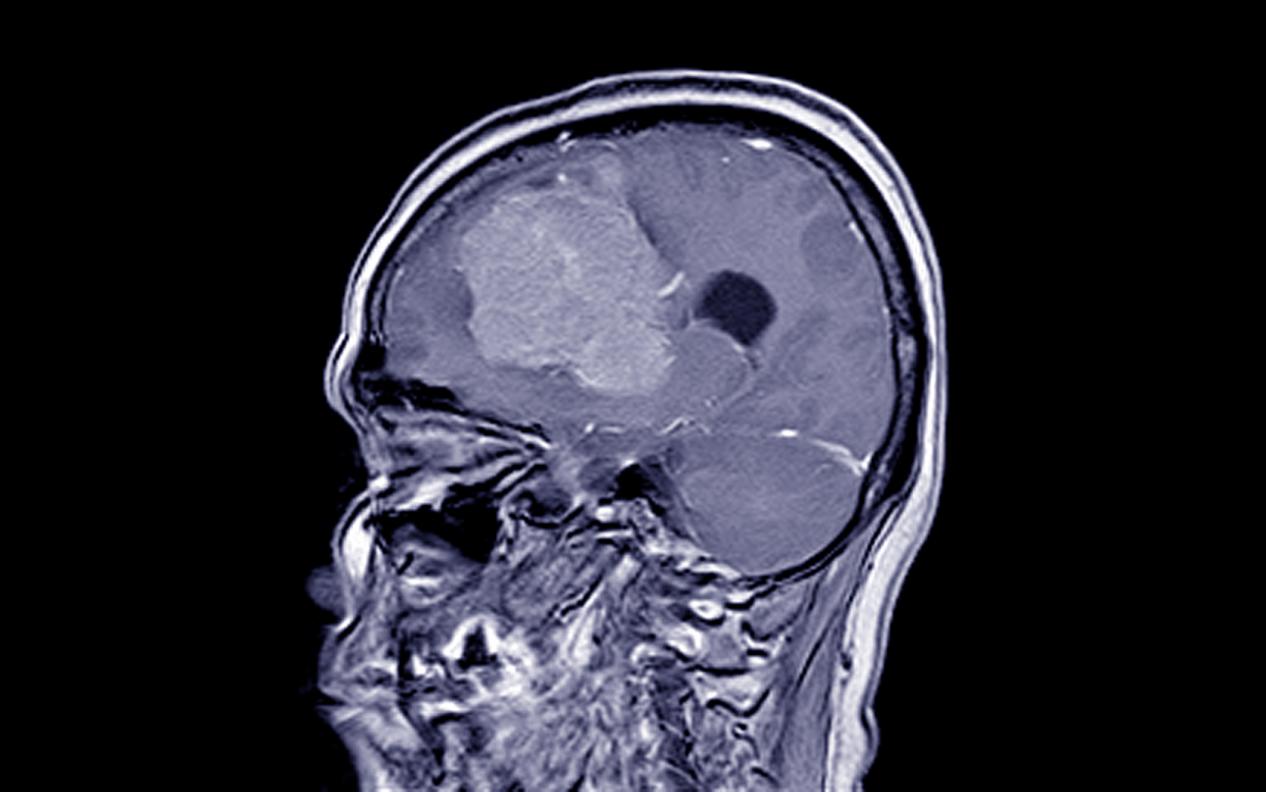

腦血管瘤的癥狀是什么和診斷方式有哪些

腦血管瘤的癥狀有哪些,達州腦血管瘤醫院哪家好-達州醫科腫瘤醫院導言:腦血管瘤是一種常見的腦部血管系統疾病,它可以在任何年...

腦血管瘤的定義和分類有哪些

什么癥狀是腦血管瘤,達州腦血管瘤醫院哪家好-達州醫科腫瘤醫院導言:腦血管瘤是指在腦部或腦膜血管系統內形成的良性腫瘤。它由...